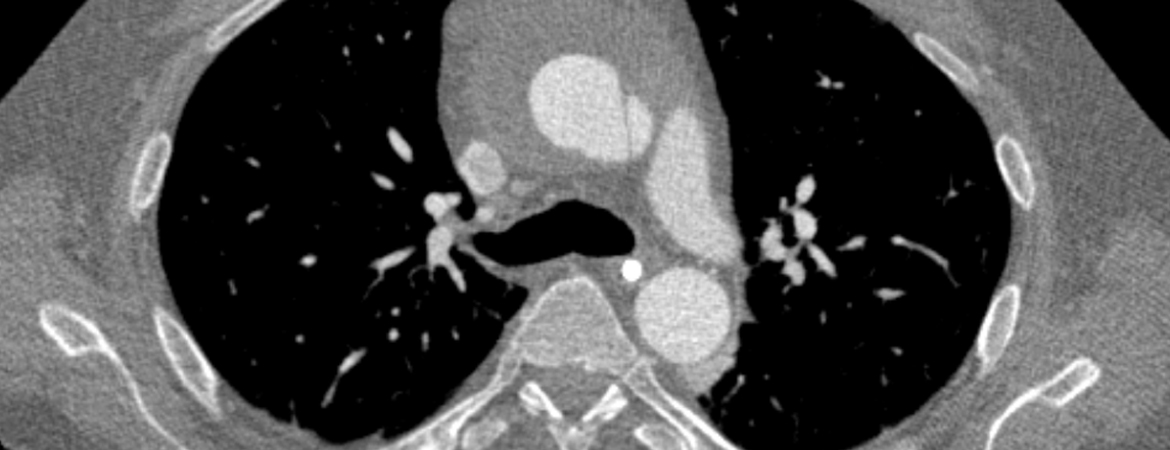

Joanna Gawinecka, Felix Schönrath, Arnold von Eckardstein (Author) Acute aortic dissection: pathogenesis, risk factors and diagnosis Fulltext PDF Fulltext HTML